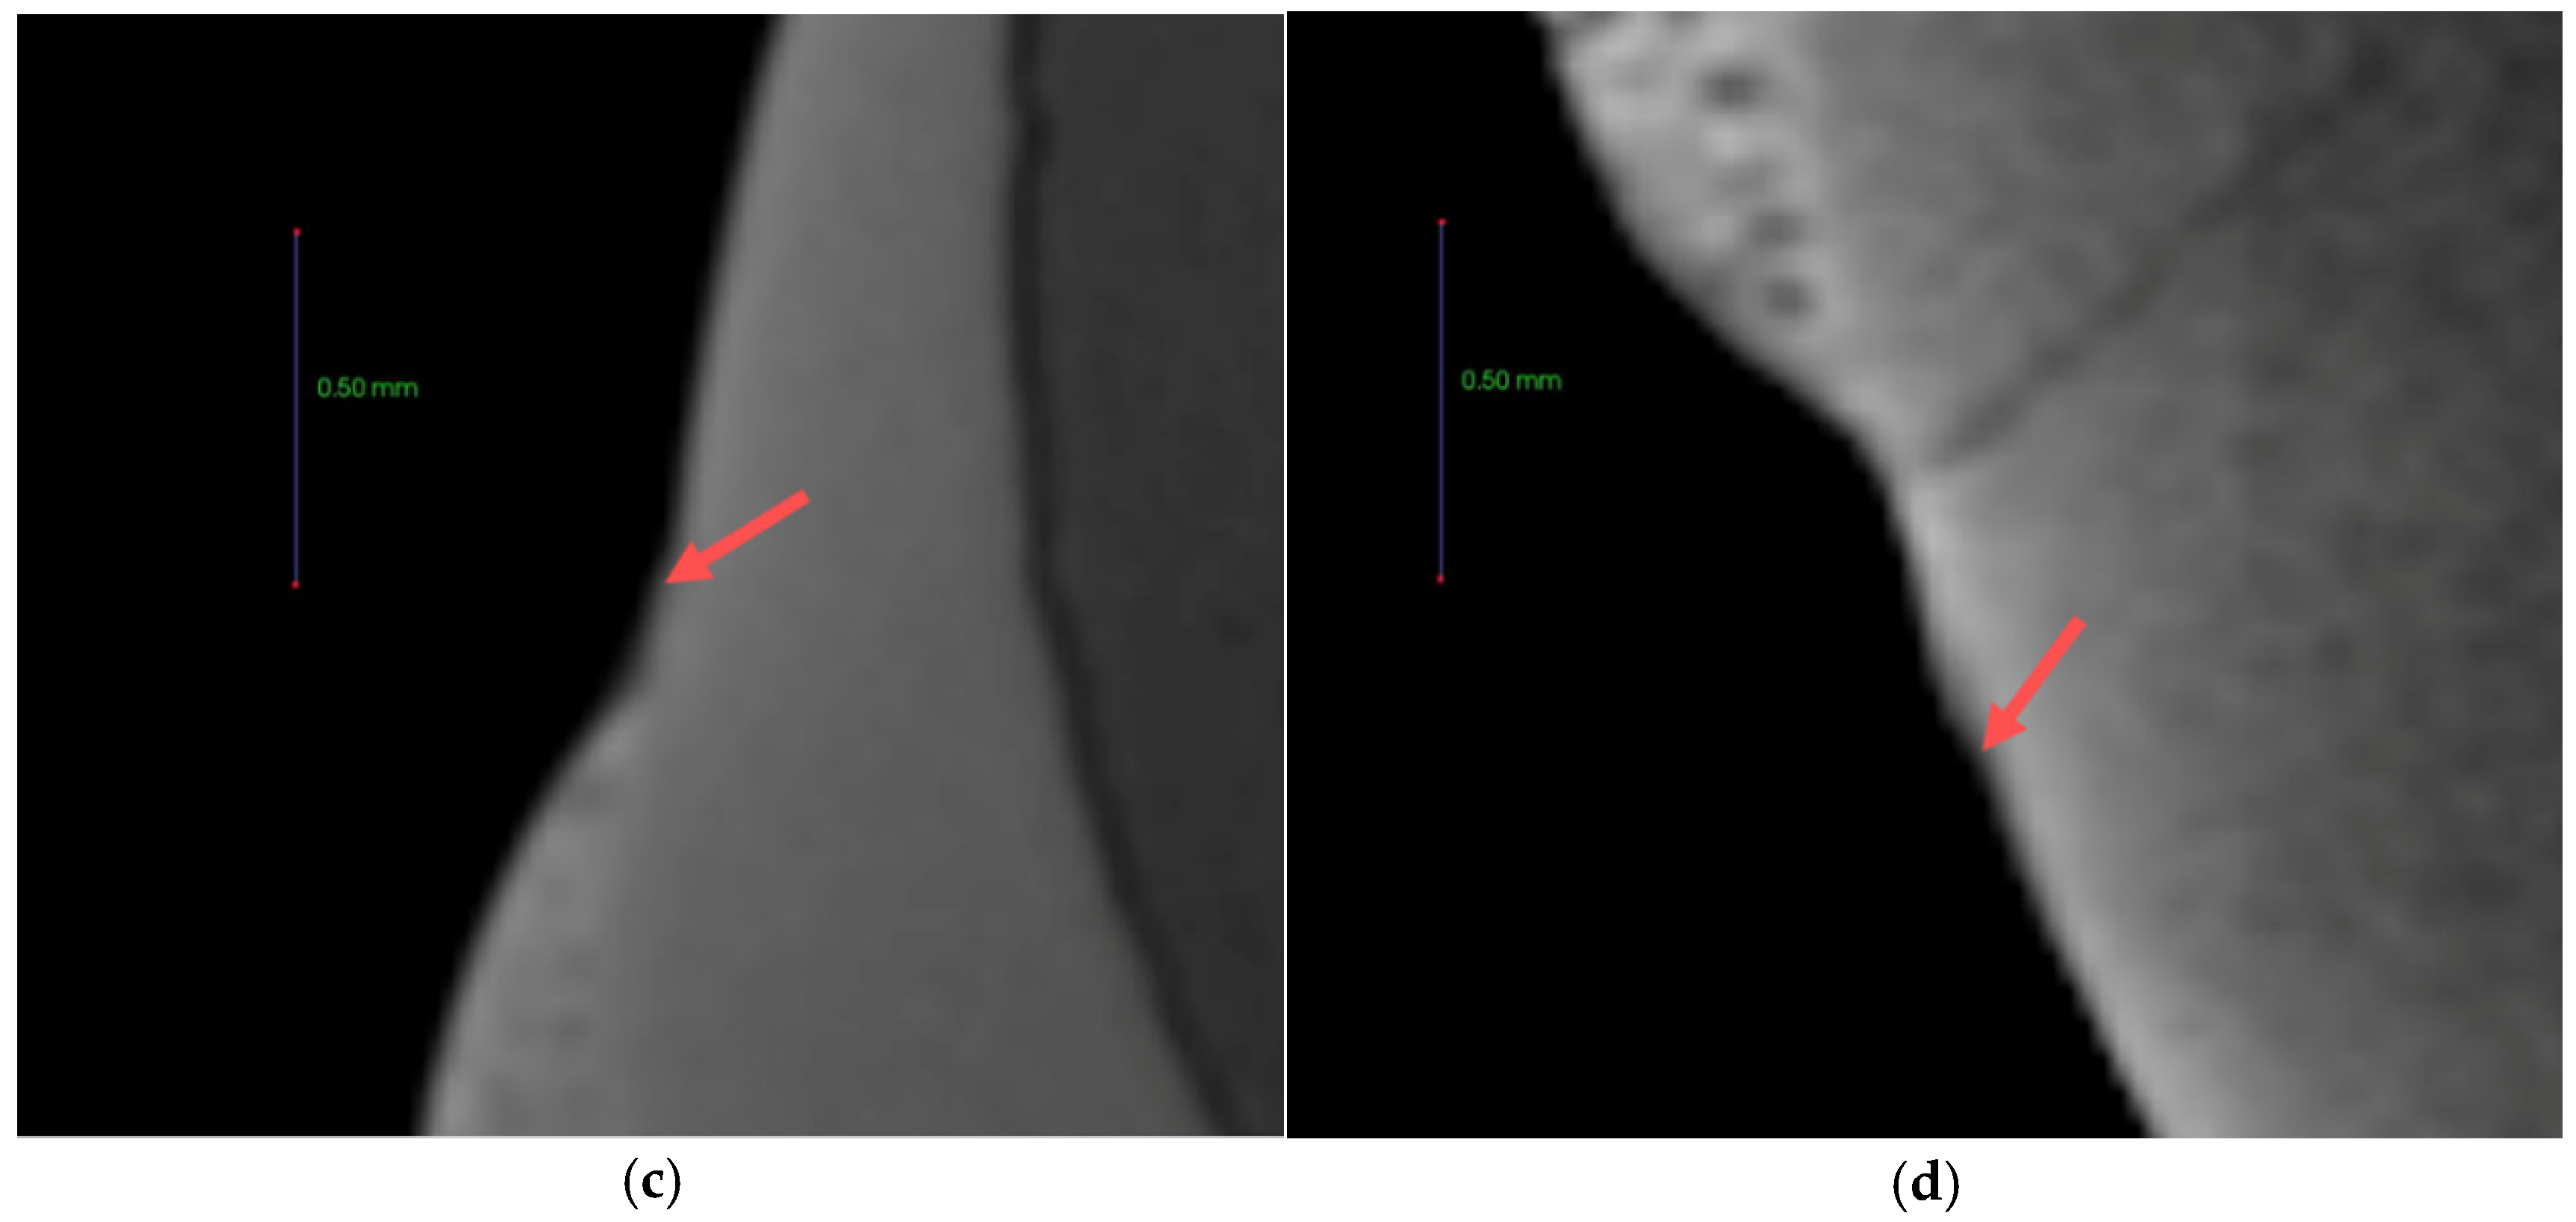

3.8. Anti-demineralization